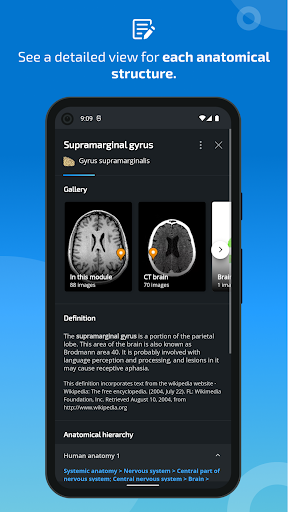

*Peningkatan tampilan detail bagian anatomi untuk memudahkan identifikasi dalam gambar modul saat ini dan modul lainnya.

tampilan detail istilah terkait struktur anatomi sekarang ditampilkan

Opsi -New untuk memperluas galeri gambar di layar informasi struktur anatomi.